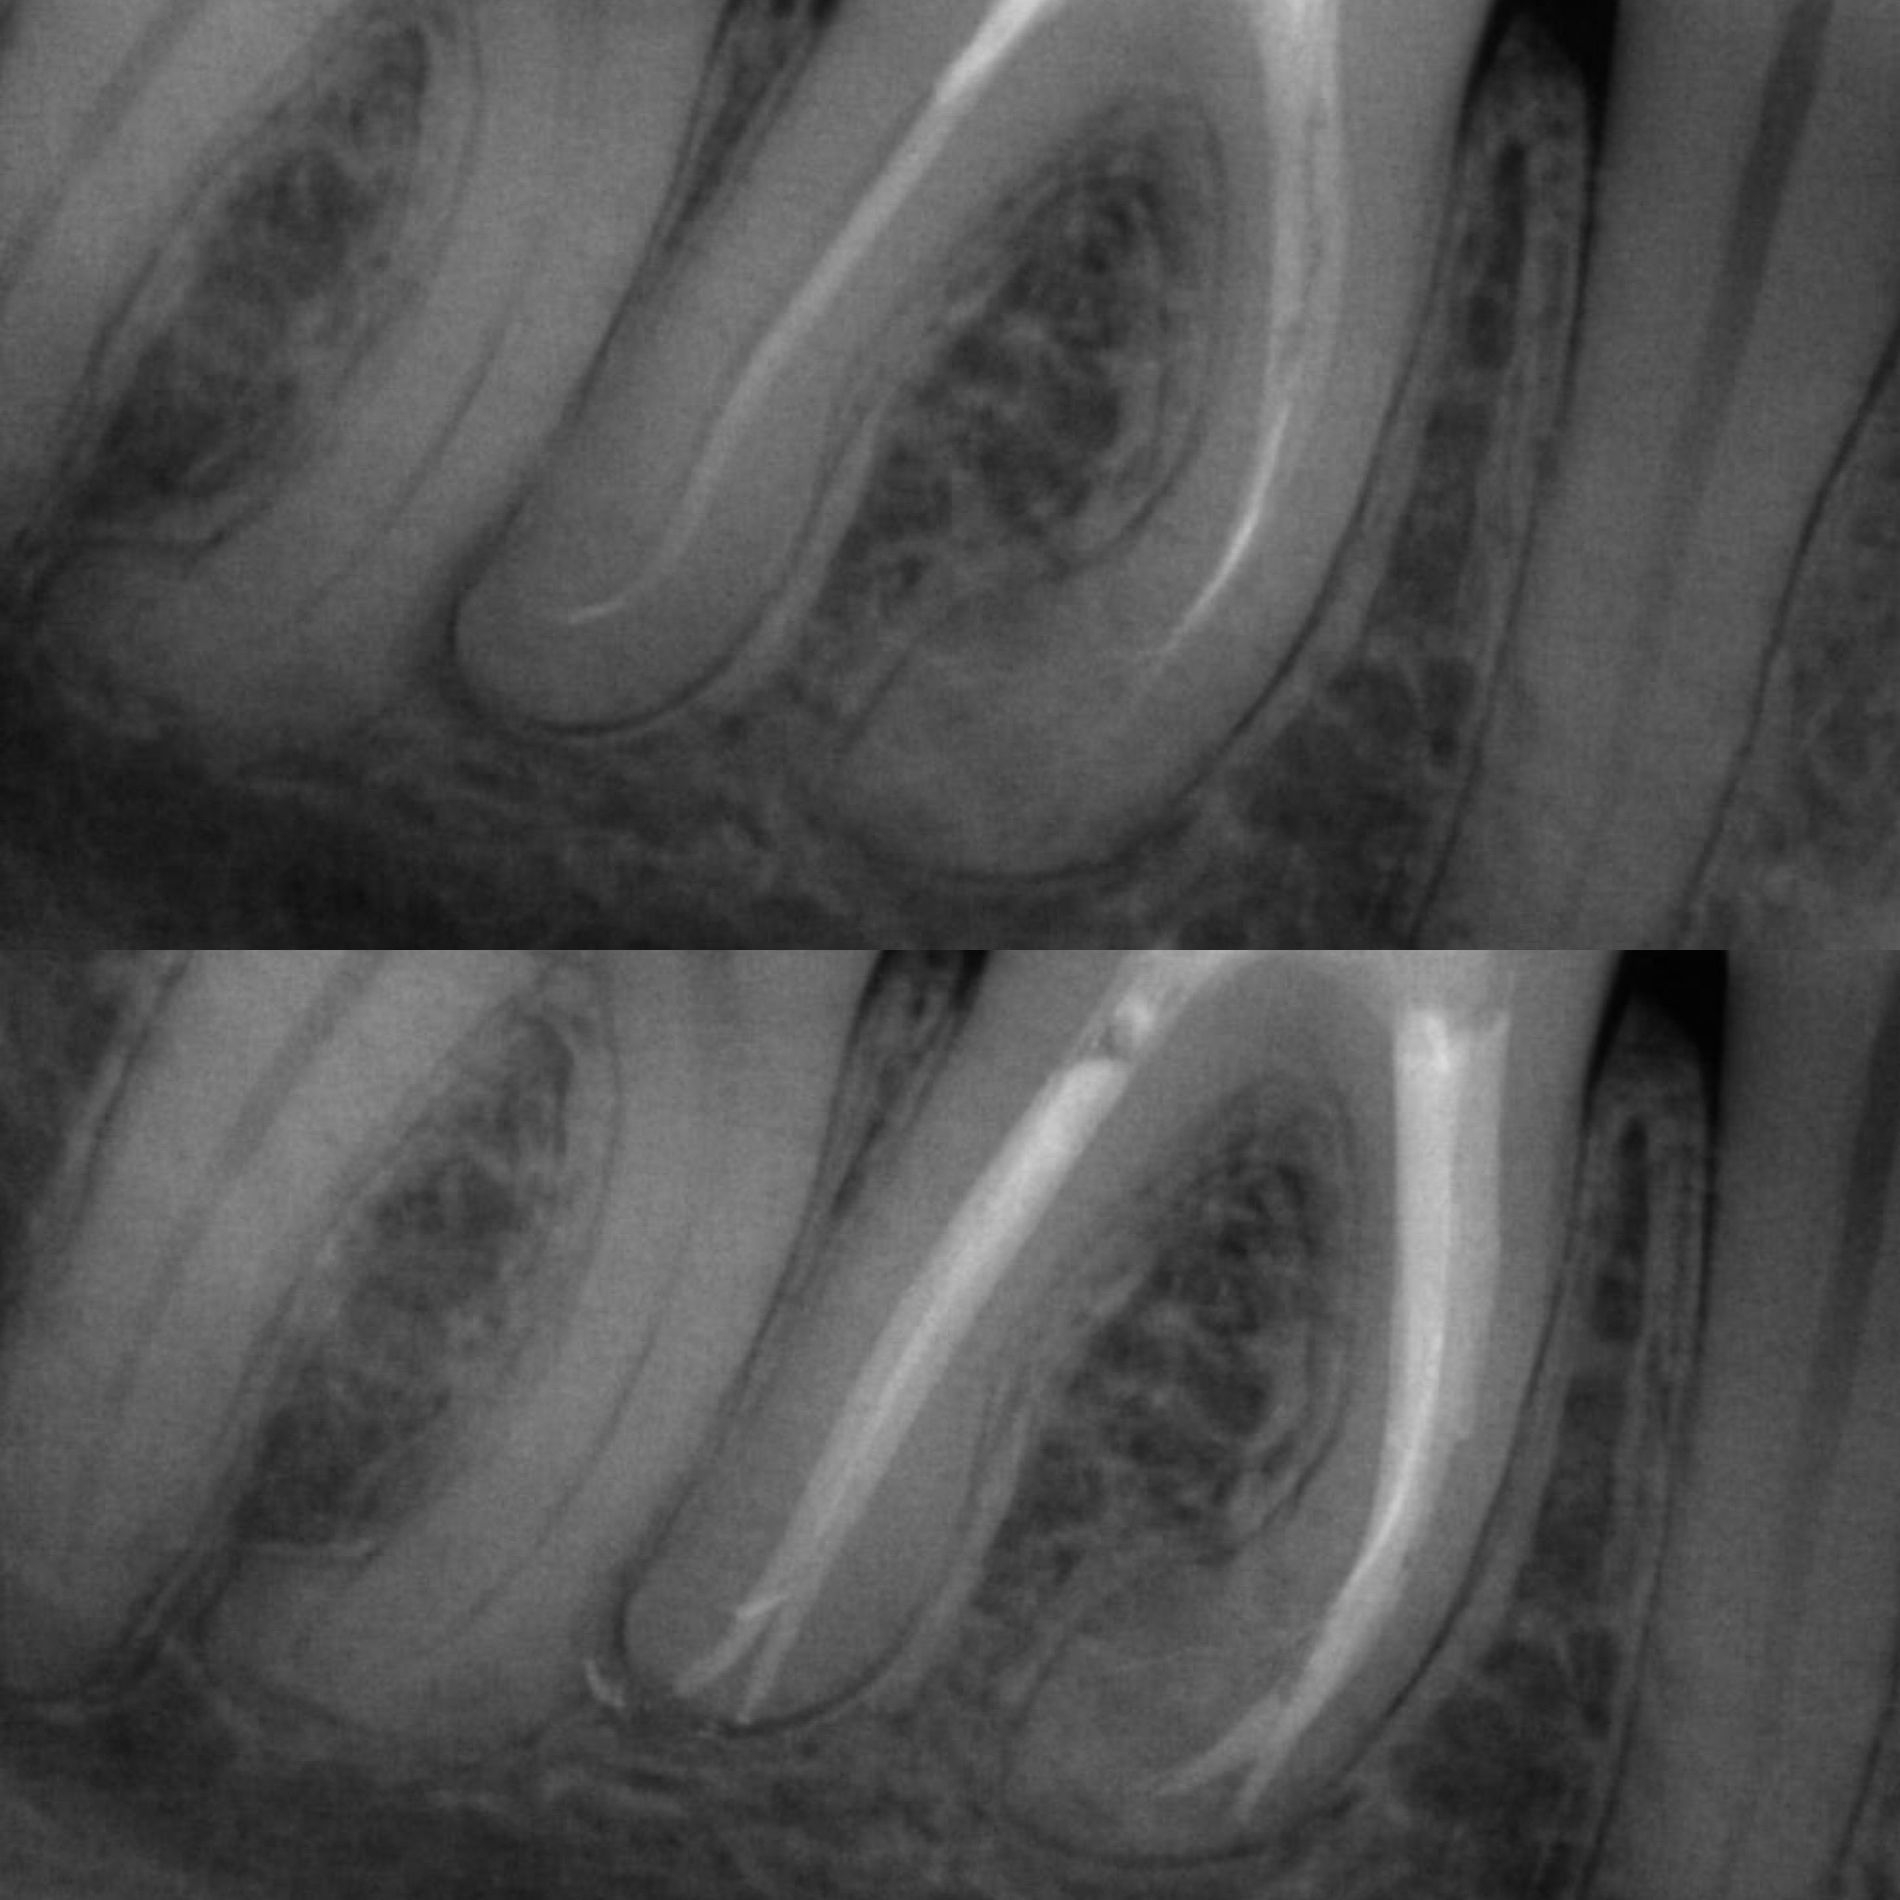

- 3D пломбирование корневых каналов горячей гуттаперчей. Высокоэффективная техника, позволяющая заполнить все ответвления корневых каналов настолько плотно, чтобы достичь абсолютной герметизации. А значит, ни одна инфекция не сможет повторно поразить корневые каналы твоего зуба.

Чтобы провести процедуру лечения и пломбирования каналов, мы в космической стоматологии Драганчука используем оптическое увеличение с помощью микроскопа Carl Zeisse.

Он позволяет вывести изображение на большой экран и масштабировать его, чтобы наша космическая команда могла осуществить все необходимые манипуляции особенно скрупулезно. Благодаря такому оптическому контролю каждого этапа лечения, мы можем оценить его эффективность и предотвратить возникновение осложнений.

Чтобы провести процедуру лечения и пломбирования каналов, мы в Космической стоматологии Драганчука используем оптическое увеличение с помощью микроскопа Carl Zeisse. Он позволяет вывести изображение на большой экран и масштабировать его, чтобы наша космическая команда могла осуществить все необходимые манипуляции особенно скрупулезно.